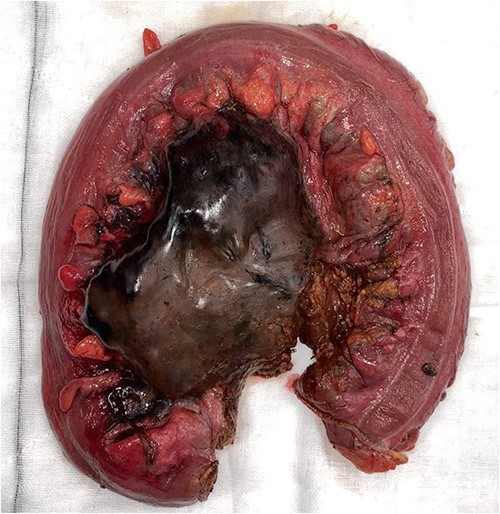

On CT of her abdomen and pelvis, there was a large volume of pneumoperitoneum and a massive sigmoid faecaloma suggestive of stercoral perforation associated with ischaemic changes (Fig. 1). She underwent emergency laparotomy, which identified a grossly dilated and redundant sigmoid colon impacted with a large, inspissated faecaloma >15 cm in diameter (see Figs 2 and 3). The perforation was identified in the mid to distal sigmoid colon with evidence of necrosis of the wall. A Hartmann’s procedure and extensive washout was performed. Post-operatively, the patient required vasopressor support for septic shock in intensive care, as well as granulocyte colony stimulating factor (G-CSF) to help in the management of her febrile neutropaenia. Her Clozapine was suspended for several days due to her neutropenia. She was given G-CSF to improve her neutropenia to improve her chances of survival as it known that immunocompromised patients with sepsis have worse prognosis [9]. Fortunately, the patient recovered well post-operatively and was discharged to rehabilitation on day 10.

Resected specimen demonstrating ischaemic necrosis and faecaloma through large stercoral perforation.

Histopathology confirmed the presence of a full thickness perforation approximately 50 mm in length, with surrounding ischaemic necrosis of the mucosa and a massive faecaloma, confirming the diagnosis of stercoral perforation associated with ischaemia. Although there have been limited case reports of stercoral perforation described in schizophrenic patients requiring Clozapine and other antipsychotics that have a constipating effect [6, 10], Ms IW had been on long-term Clozapine and her stercoral perforation was believed to be associated with her comorbidities and adjuvant chemotherapy, not just associated with Clozapine.